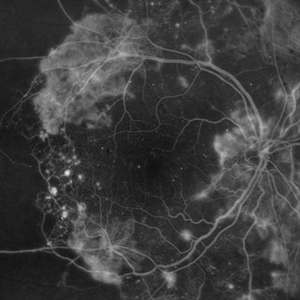

PROLIFERATIVE DIABETIC RETINOPATHY

EARLY PHASE FLUORESCEIN ANGIOGRAPHY OF A 50 YEAR OLD MALE WITH PROLIFERATIVE DIABETIC RETINOPATHY

Photographer: Dr. Akansha Sharma-Retina Foundation, Ahmedabad

Condition/keywords: florid type PDR, proliferative diabetic retinopathy (PDR)